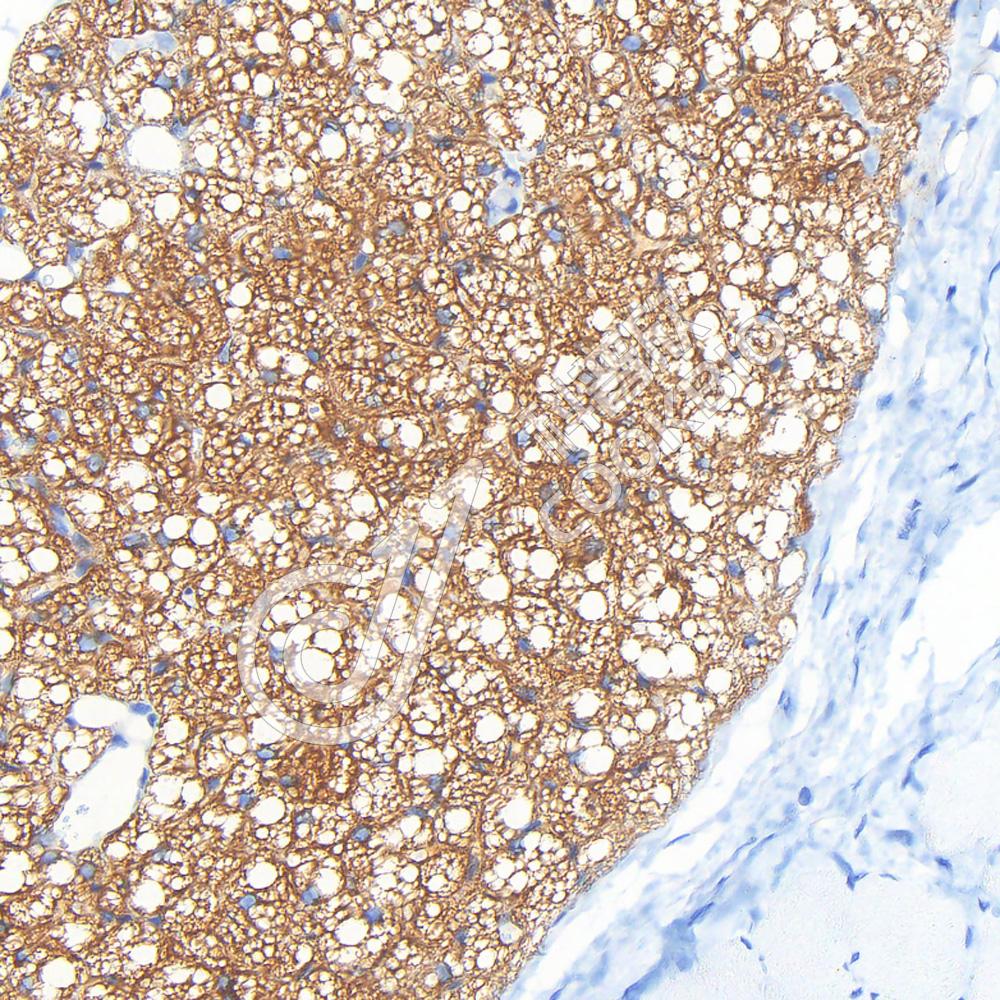

IHC检测UCP1蛋白(货号 K5456522).

样品: 小鼠棕色脂肪, 4%多聚甲醛 (货号KSG1101) 固定12-24小时.

抗原修复: 柠檬酸抗原修复液(干粉, pH 6.0) (KSG1201), 高压锅均匀喷气计时2分钟.

—抗: 1: 700稀释, 4℃ 孵育过夜.

二抗: S-vision免疫组化多聚二抗(山羊抗兔),即用型 (货号KB3906), 室温孵育20分钟.

样品: 大鼠棕色脂肪, 4%多聚甲醛 (货号KSG1101) 固定12-24小时.